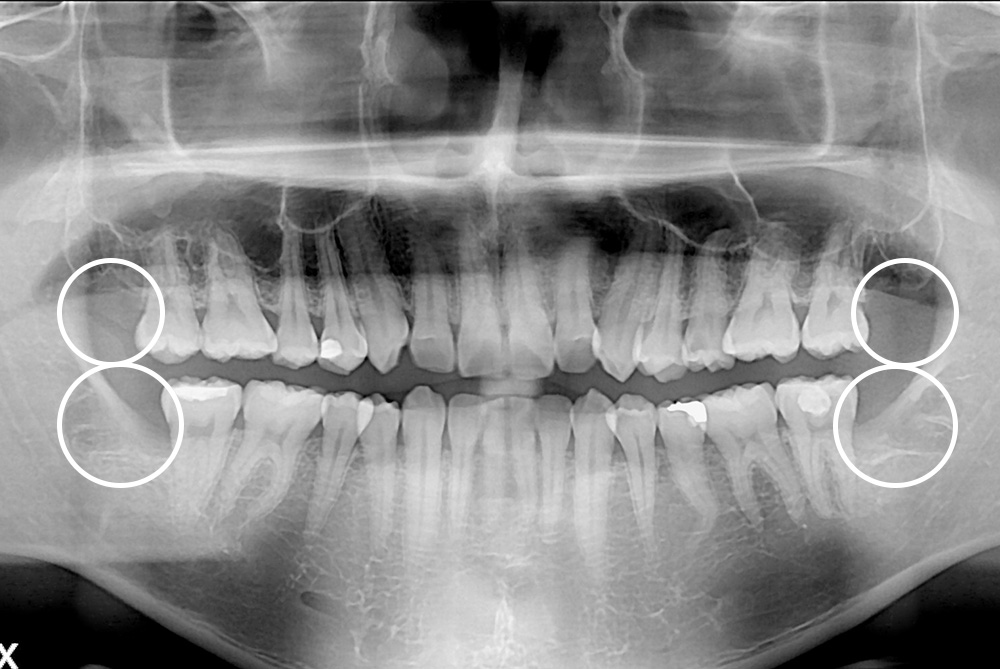

[사랑니] 매복 사랑니 발치

치료전 : 2017-08-25